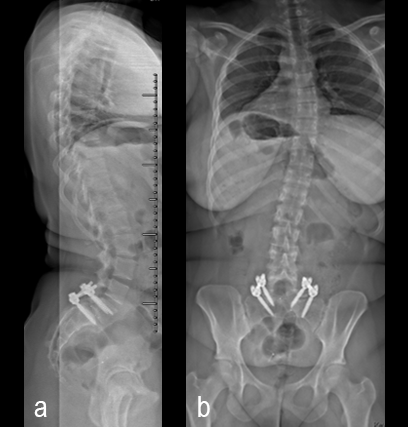

A 17-year-old girl presented to the spine clinic with significant low back pain. X-ray, CT and MRI imaging (Figs 1-3) showed evidence of spondylolisthesis. Upon clinical examination of spinal alignment, the patient was found to have a pelvic incidence of 78°, a lumbar lordosis of 54°, and a pelvic tilt of 51°.

Posterior spinal instrumentation and fusion (PSIF) was undertaken with an interbody fusion at L5-S1. L5 laminectomy and sacral dome osteotomy followed by pedicle screw instrumentation using TriALTIS™ implants helped reduce the lumbosacral kyphosis and translation of L5-S1 and promote fusion across this level (Fig 4a-b).